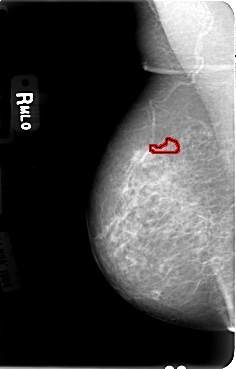

B_3030_1.RIGHT_MLO

FILE: B_3030_1.RIGHT_MLO.OVERLAY

TOTAL_ABNORMALITIES 1

ABNORMALITY 1

LESION_TYPE CALCIFICATION TYPE PLEOMORPHIC DISTRIBUTION CLUSTERED-LINEAR

ASSESSMENT 4

SUBTLETY 3

PATHOLOGY BENIGN

TOTAL_OUTLINES 1

BOUNDARY